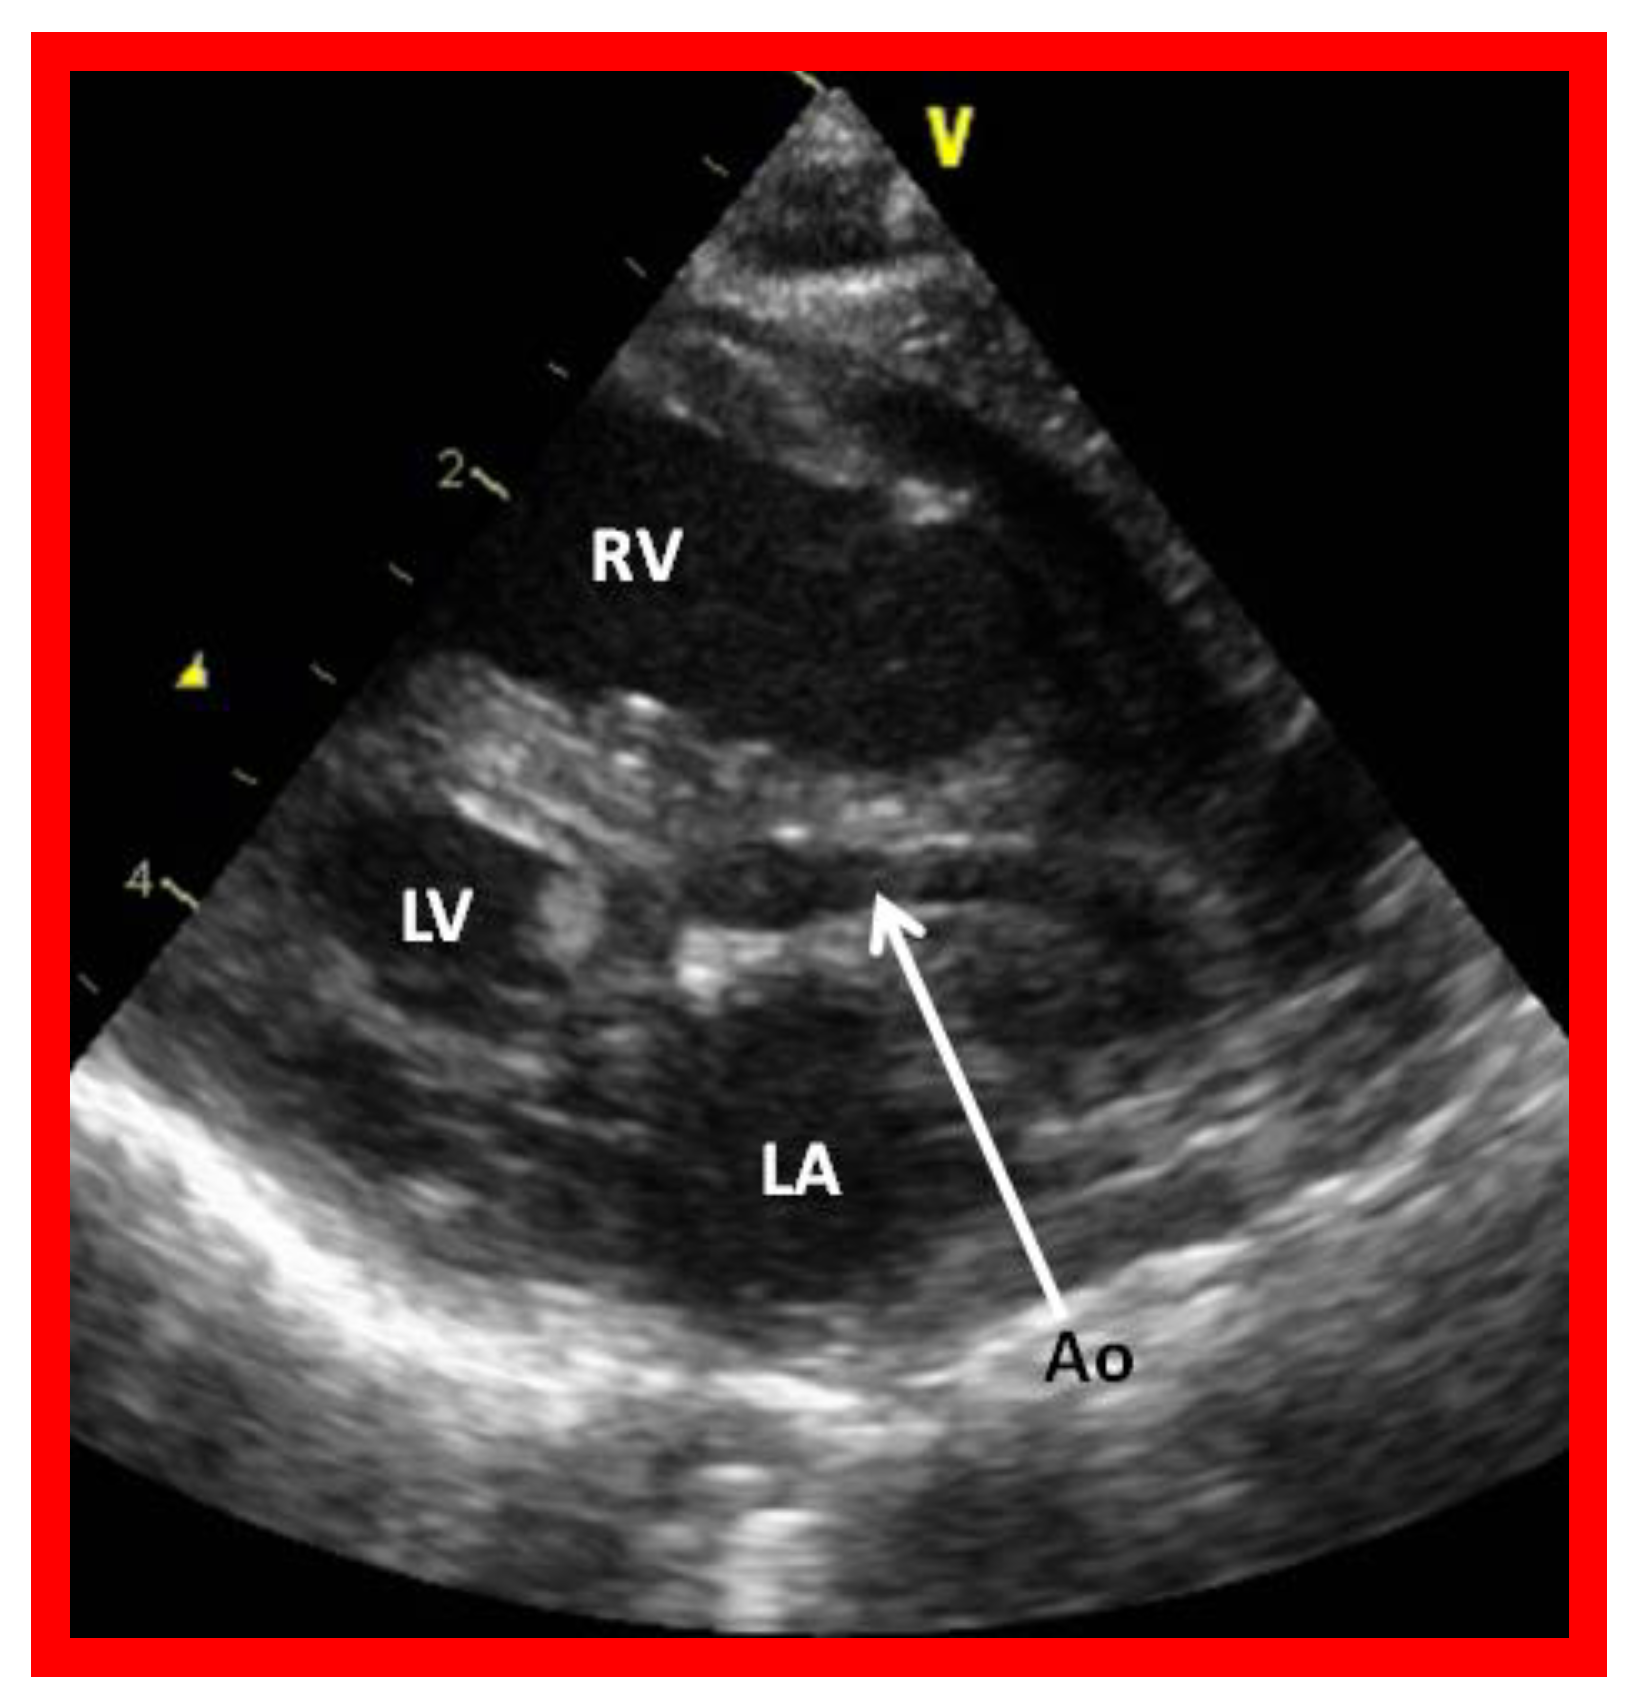

Figure 2.

Echocardiogram in a parasternal long short axis view of a baby with hypoplastic left heart syndrome illustrates a small left ventricle (LV), a severely hypoplastic aorta (Ao) (arrow), and an enlarged right ventricle (RV). LA, left atrium.